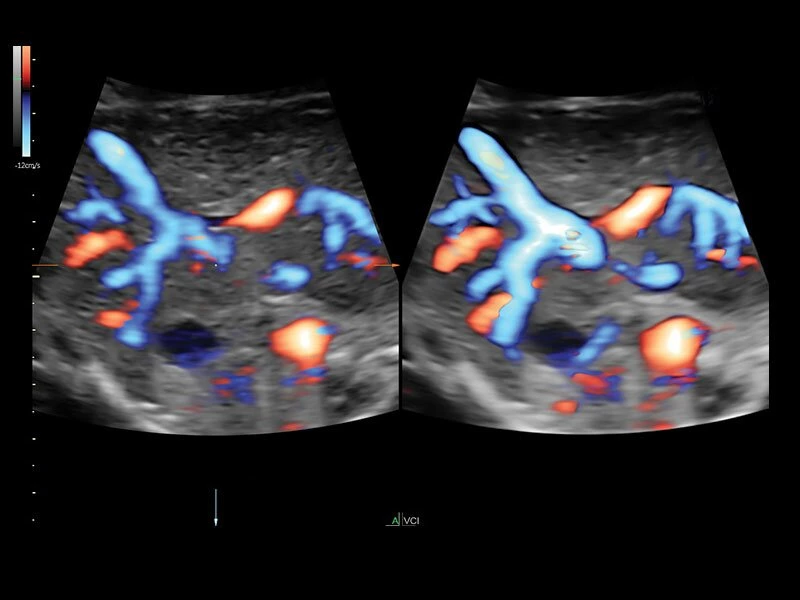

Она оснащена инструментами, которые упрощают получение изображений, отличается высокой чувствительностью цветового допплера, поддерживает инновационные 3D/4D технологии.

- Технология HDlive Flow — повышает реалистичность визуализации сосудистых структур, улучшая восприятие глубины (по сравнению с традиционным цветовым допплером и функцией HD-Flow).

- Усовершенствованный режим объемной визуализации с контрастированием (Volume Contrast Imaging, VCI) и опция OmniView

- Повышает контрастное разрешение и улучшает визуализацию области интереса в любой плоскости сечения, даже при исследовании структур неправильной формы.

- HD-flow или, так называемый, высокочувствительный тканевый допплер.

- Возможность визуализации тока крови в B-Flow (недопплеровский режим).